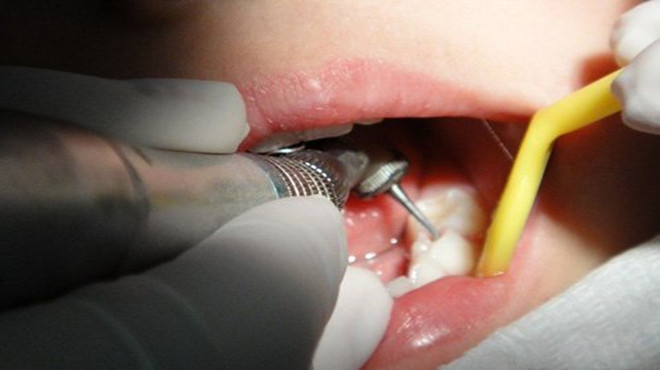

1、由于被蛀虫侵蚀的牙齿病发的时间上不能确定,很容易被患者所忽视,这是极其危险的,此类疾病只会越拖越严重,患者须按照口腔医生的建议对牙齿进行科学有效的系统化治疗,才能拥有一口洁白的牙齿。

如果龋齿严重,要到医院口腔科检查,有龋洞尽量修补。